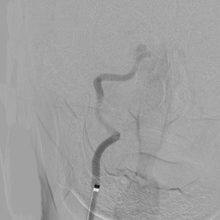

ソリティア(ステント型血栓除去器具)による超急性期血管内治療

突然の意識障害と左半身重度麻痺で発症した右内頚動脈閉塞例。発症から5時間が経過しており、t-PA 治療の適応外であったため緊急で血管内治療を施行。治療開始後速やかに完全再開通を得た。術後左麻痺は残存したが意識障害は回復。

1.緊急MRA検査で右内頸動脈閉塞の診断

2.治療前造影で右内頸動脈の完全閉塞を認める

3.閉塞部遠位までマイクロカテーテルを誘導し造影

4.ソリティアを閉塞部まで誘導し展開

5.手技開始速やかに完全再開通を得た